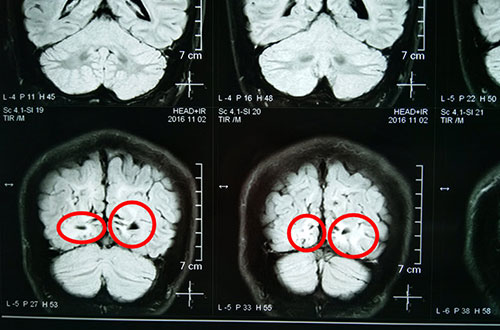

术前影像资料:红圈内为异常信号灶

术前影像资料:红圈内为异常放电区

11月2日行MR头颅平扫+SWI,灰白质对比成像示:双侧枕叶异常信号伴脑白质量减少。